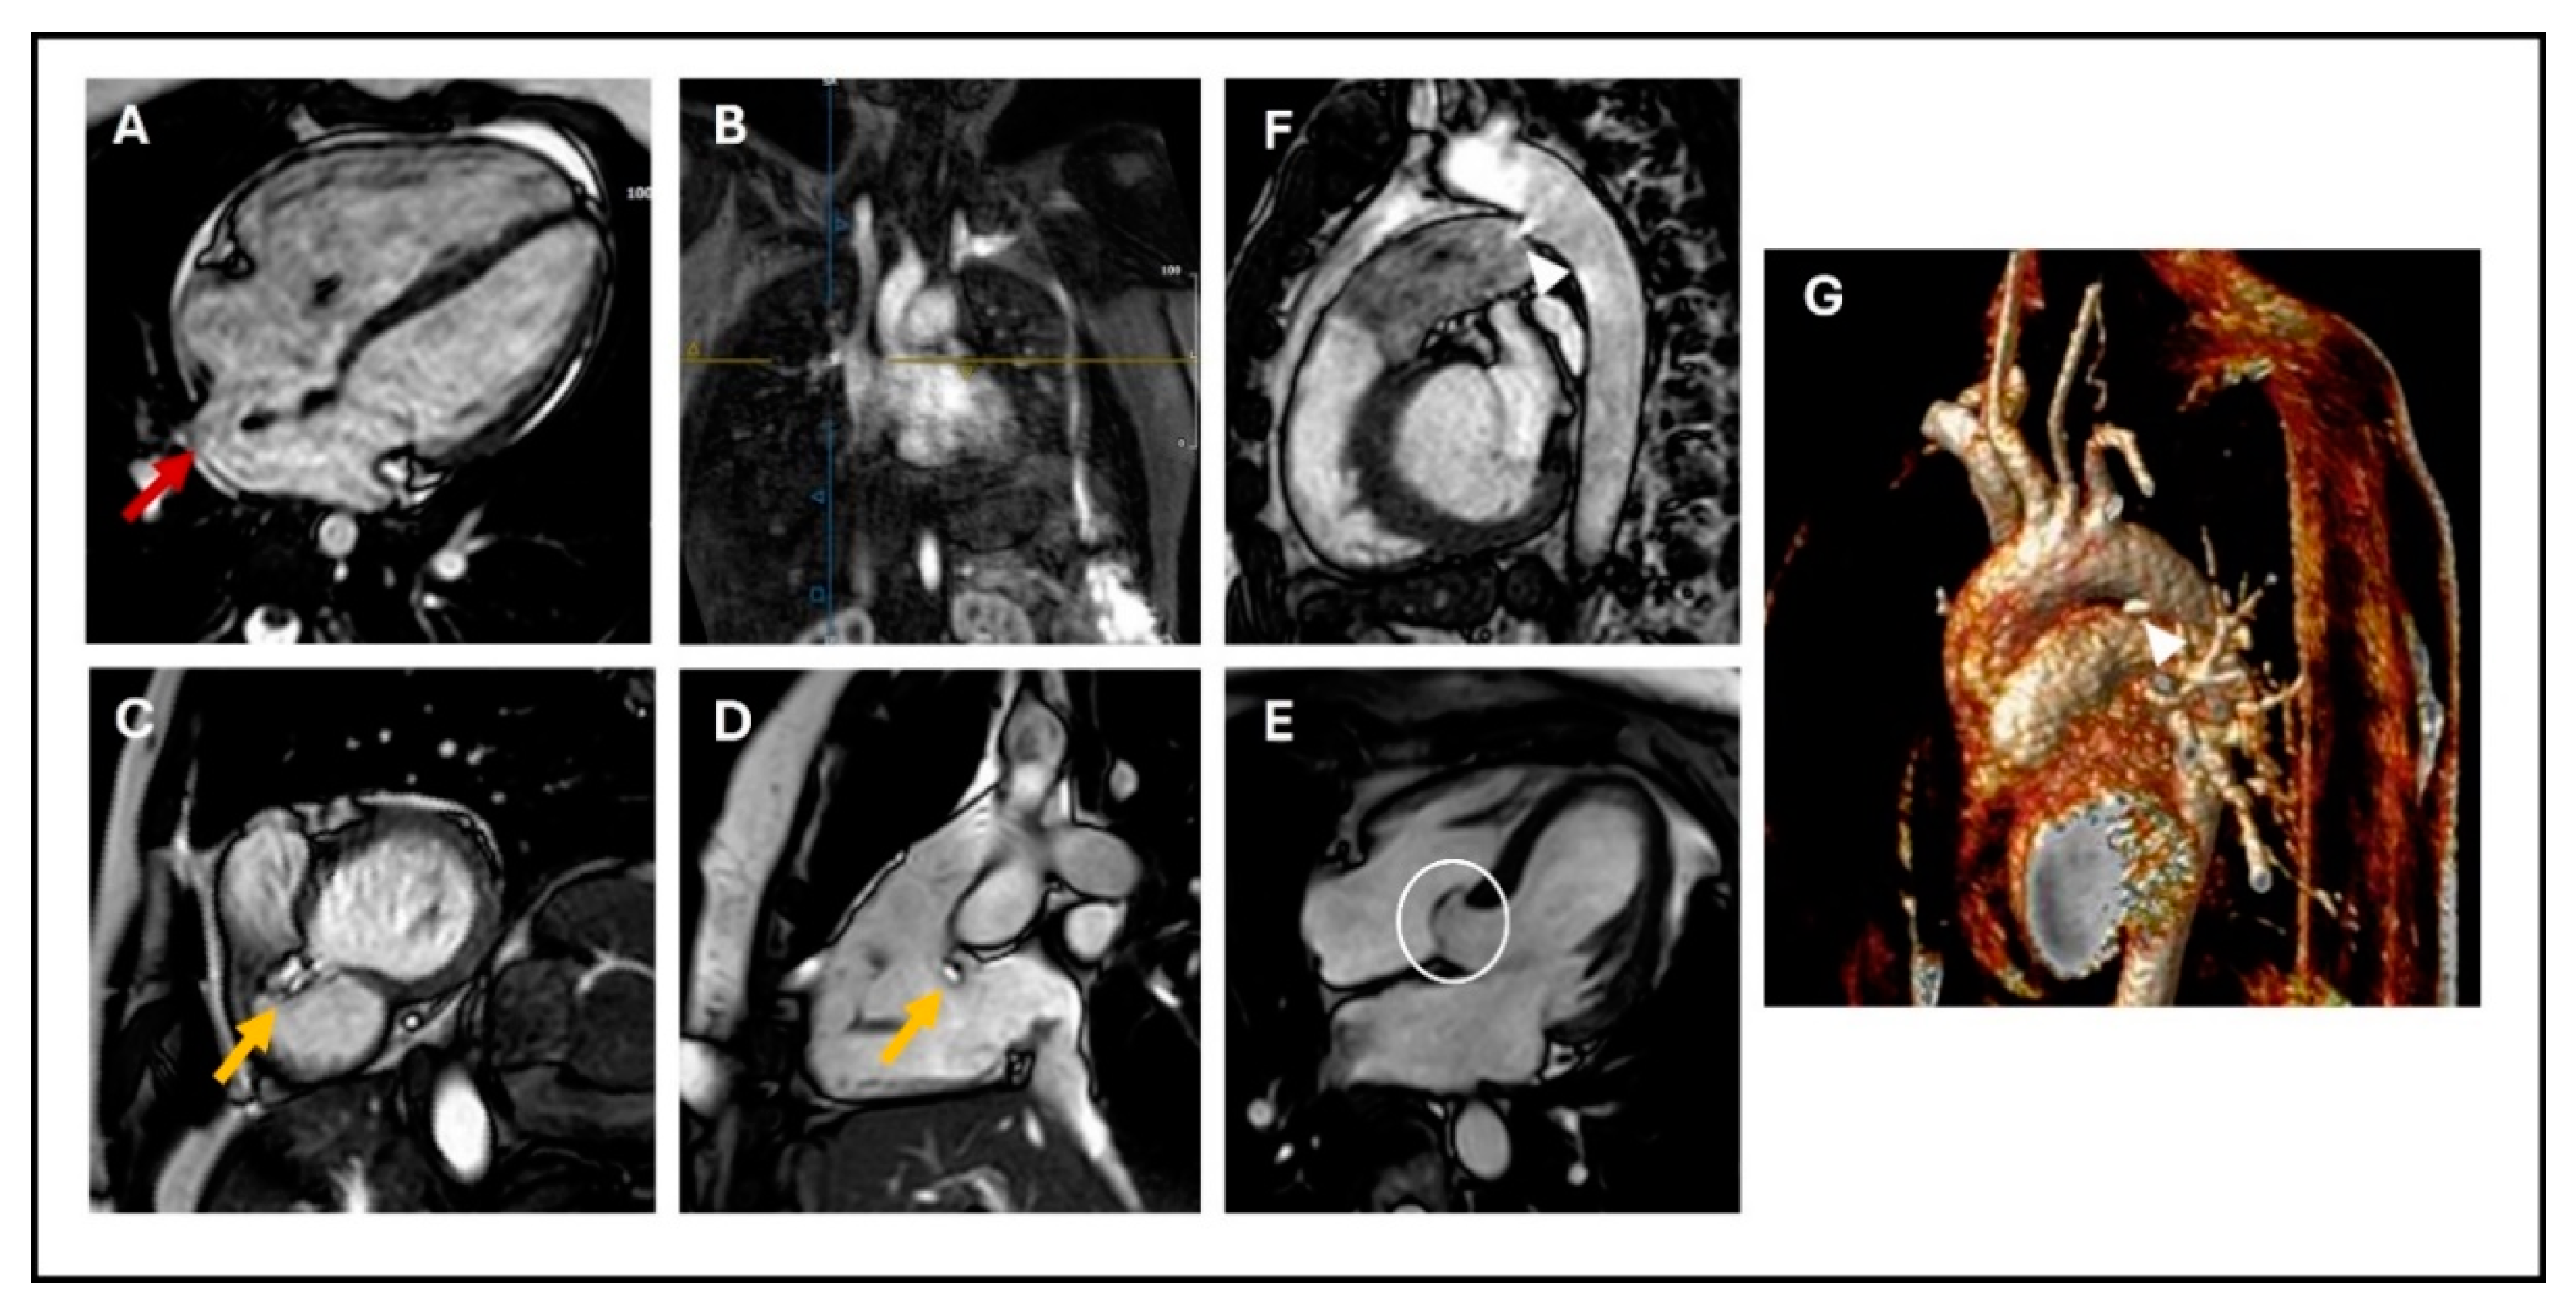

2.2.3. Tetralogy of Fallot